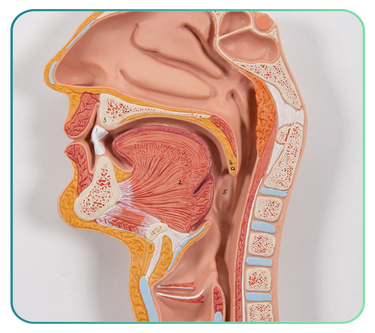

Enhance medical education with our collection of digestive system anatomical models including the stomach, liver, gallbladder, pancreas & colon models. Discover the anatomy of healthy organs as well as common gastrointestinal diseases such as stomach ulcers, gallstones and liver cirrhosis. Our digestive system anatomy posters are ideal for study and patient education.

At AnatomyStuff we stock a diverse range of digestive system anatomical models to suit your training needs. From budget models and affordable medical education posters to highly advanced 3D printed bowel models, you can transform medical training and patient education. As well as our own exclusive collection, we are proud resellers of 3B Scientific, Anatomy Lab, Denoyer-Geppert Science Company, ESP Models, Erler Zimmer and GPI Anatomicals. Explore our exclusive collection of digestive system anatomy charts, posters, fine art prints and digital anatomy study guides. Discover the anatomy of key organs like the liver, stomach, pancreas and bowel as well as the pathophysiology of common conditions like peptic ulcer disease, coeliac disease, IBD and much more. We have anatomy posters suitable for school children all the way up to medical degree level. From a liver anatomy poster to a digital study guide all about common GI disorders, find exactly what you need right here to enhance medical training and patient education.